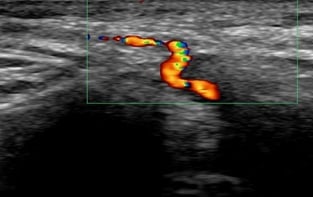

Ultrasound of the temporal arteries is used to help diagnose GCA, because it can non-invasively visualize characteristic features of the disease. Specifically, ultrasound can detect a "halo sign," which is a thickening of the artery wall, as well as stenosis (narrowing) or occlusion (blockage) of the artery. These findings can help confirm or exclude the diagnosis of GCA, potentially avoiding the need for a temporal artery biopsy in some cases.